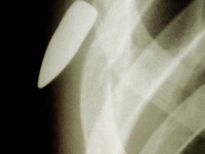

Bu röntgenler gerçek!

Bu röntgenler gerçek! galerisi resim 1